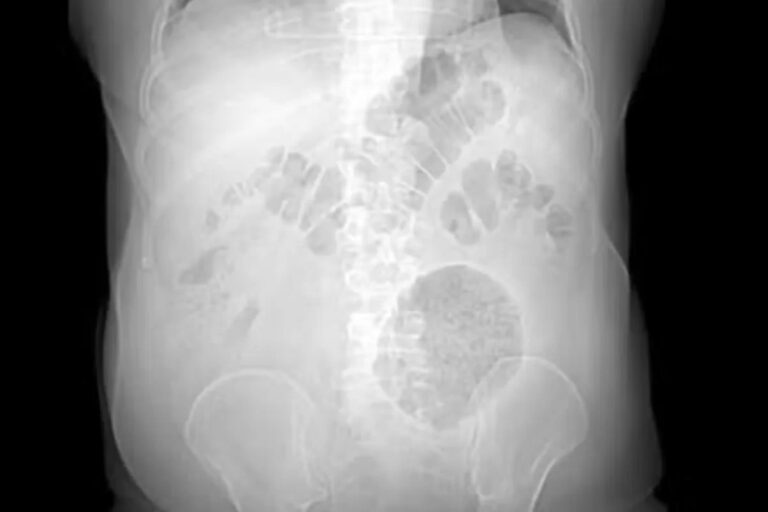

Uma tomografia computadorizada mostrou que ele tinha uma massa flácida, palpável e dolorosa no flanco esquerdo do abdome. Mas foi o tamanho dessa massa que chamou a atenção do médico Leonardo Fiuza, responsável pelo atendimento laboratorial.

Os divertículos costumam medir até 4 cm. Em casos mais raros, chegam a 9 cm. O do paciente do HMSF tinha 13 cm.